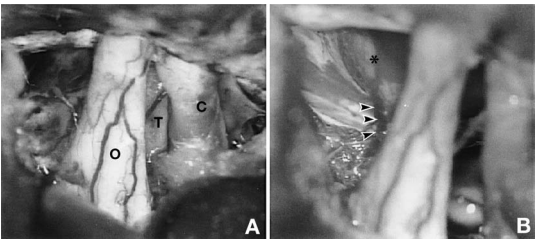

手术采用右侧额颞开颅。进入鞍上区后,见肿瘤位于右侧颈内动脉内侧、视神经下方(图 2A)。磨除前床突并切开视神经管后,将肿瘤与颈内动脉分离。穿刺囊腔抽出透亮、似脑脊液样液体。肿瘤实性部分为轴外病变,呈红褐色,质地富有弹性。肿瘤位于蛛网膜下腔,与垂体柄轻度粘连,但易于分离。肿瘤全切除后,垂体柄及鞍隔保持完整(图 2B)。

图2.A:肿瘤切除前术中照片。肿瘤(T)位于右侧颈内动脉(C)内侧、右侧视神经(O)下方。B:肿瘤切除后术中照片。垂体柄(箭头所示)及鞍隔(星号所示)保持完整。